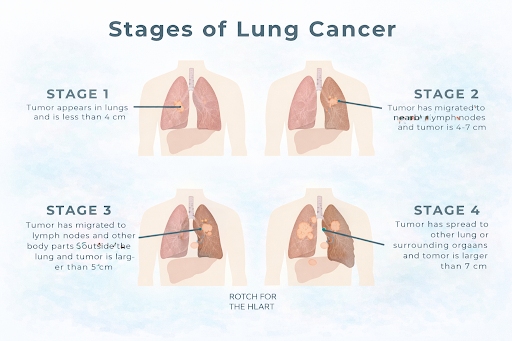

What is Lung Cancer?

Lung cancer is a type of cancer that begins in the lungs, the organs responsible for breathing. It occurs when abnormal cells in lung tissue grow uncontrollably and form tumours, which can interfere with normal lung function and may spread to other parts of the body.

Lung cancer is a type of cancer that begins in the lungs, the organs responsible for breathing. It occurs when abnormal cells in lung tissue grow uncontrollably and form tumours, which can interfere with normal lung function and may spread to other parts of the body.

How It Develops?

Lung cancer usually develops when normal lung cells undergo changes in their genetic material (DNA). These altered cells may begin to multiply uncontrollably, forming a tumour. Over time, cancer cells may invade nearby tissues or spread to distant organs.